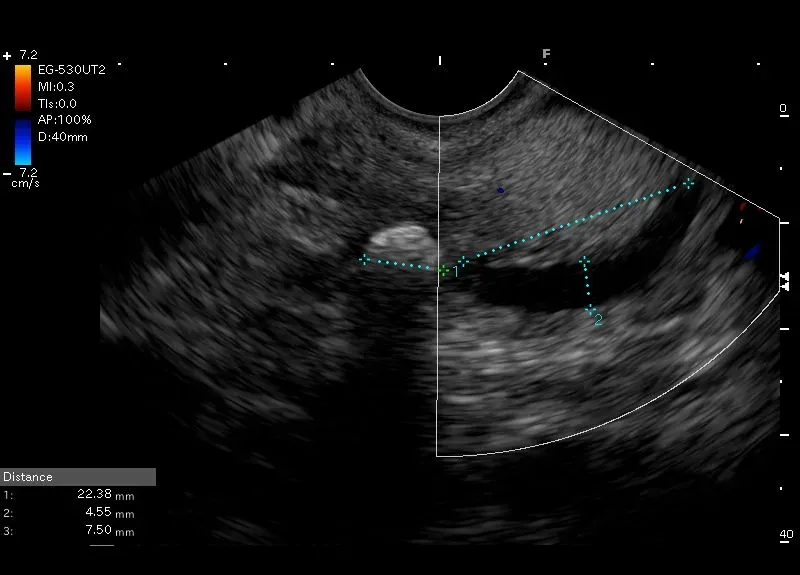

W świetle przybrodawkowego odcinka przewodu Wirsunga, tuż przy brodawce Vatera widoczne jest hyperechogeniczne, owalne ognisko wielości 9/7 mm z cieniem akustycznym – obraz odpowiadający złogowi w przewodzie Wirsunga.